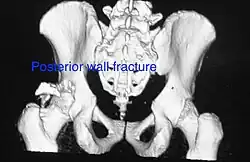

Posterior wall fracture as seen on 3-D CT scan -

| Posterior wall | This is the most common variety of acetabular fracture. It typically occurs due to dashboard injury; when a person travelling in a vehicle involved in a head-on collision, the force applied over the flexed knee travels along the femur bone to the head of the femur, breaking the posterior wall of the acetabulum. The head of the femur is dislocated outside the joint. | T shape | When a transverse fracture also had a vertical fracture line, it is called a T shape fracture. Here the innominate bone is broken in such a way that all three parts of it, the ilium, the ischium and the pubis are separated from one another. This is a three part fracture. Though both columns are broken, the weight bearing dome is still attached to the main part of the ilium and hence it is not a true fracture of both columns.

- Posterior wall fracture: Iliac oblique and obturator oblique views